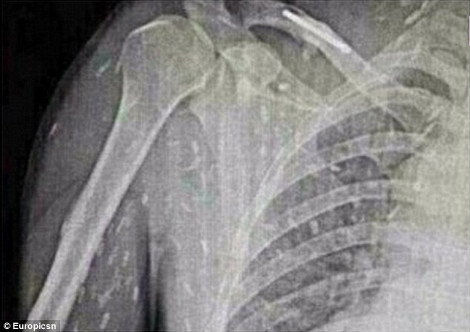

Σύμφωνα με τη Daily Mail, ένας άνδρας επισκέφθηκε τον γιατρό του στην επαρχία Guangdong της ανατολικής Κίνας, έπειτα από στομαχικούς πόνους κι έντονη φαγούρα. Προς μεγάλη του έκπληξη ανακάλυψε ότι στις ακτινογραφίες στις οποίες είχε υποβληθεί, διακρίνονταν εκατοντάδες σκουλήκια να «αλωνίζουν» στο έντερό του και σε άλλα ζωτικά όργανα. Αιτία, σύμφωνα με τους γιατρούς, δεν είναι άλλη από την κατανάλωση χαλασμένου ωμού ψαριού, δηλαδή σούσι. Ο ασθενής εισήχθη στο νοσοκομείο για θεραπεία.